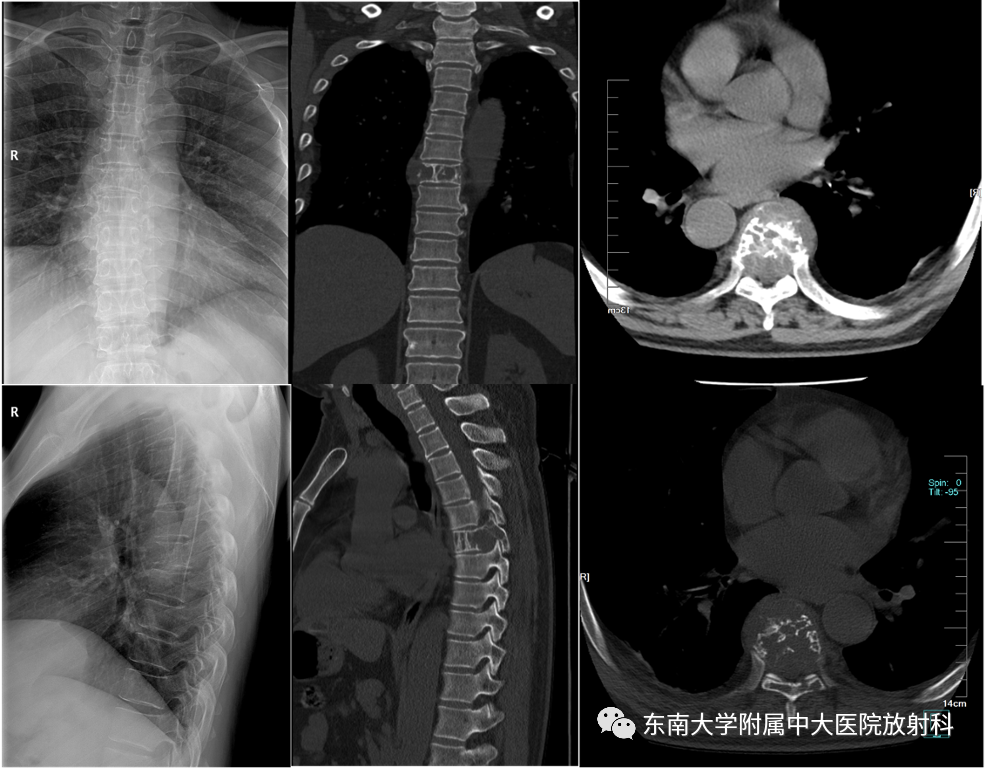

男,51岁

主诉:腰背部疼痛伴行走困难进行性加重10月

辅助检查:免疫球蛋白定量分析正常,尿轻链KAPPA LAMBDA定量:尿KAP:12.9mg/L↑。M蛋白分析:检出κ型IgG单克隆免疫球蛋白抗体